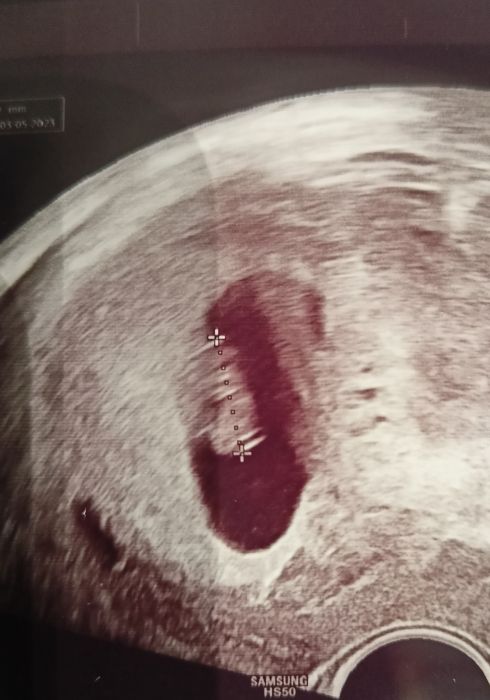

Ahoj holky,tak už máme také po kontrole -Broucek odpovídá výpočtu podle MS (poslední 28.7.),tzn 7+6 a ❤️ tlouklo jako divé ,je to ohromná úleva ??.TP mi vychází na 4.5.,ale nejspíš mi ho naplánují ještě na duben,i tak bych už zůstala tady v Kvetnatkach,jestli nejste proti ?.

Tak já dnes kontrola. Jsem 6+0 TP 17.5 kontrola 12.10 a průkazka. Srdíčko bilo